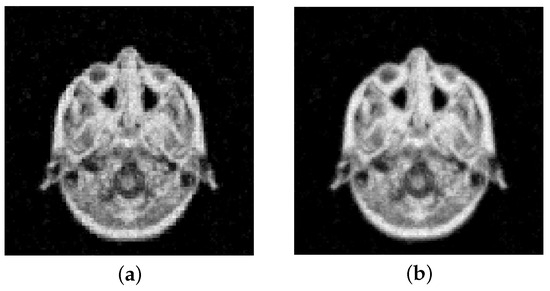

Finally, we consider a more realistic image. This is a slice taken from an anisotropic 3D MRI volume that simulates the scan of a human brain present in the MRI dataset in MATLAB. In this case, the image is composed of pixels; see Figure 8. We irradiate the image with 181 parallel rays at 90 equispaced angles between 0 and . This produces a matrix . We corrupt the data with white Gaussian noise, resulting in the sinogram shown in Figure 8b.

Figure 8.

MRI image test problem: (a) True image ( pixels), (b) noisy sinogram (5% Gaussian noise).

We report the evolution of the RRE against the iterations in Figure 9. We can observe that the results are very close to the ones obtained for the Shepp–Logan phantom. In particular, gives more stable convergence, while higher-order projectors provide slightly better reconstructions. This can also be seen from the results reported in Table 2 and Figure 10. The latter shows the computed solutions by the MGM using and , each stopped at the discrepancy principle iteration.

Figure 10.

MRI test image with 5% noise. Reconstructions obtained at the DP iteration: (a) MGM, , (b) MGM, .